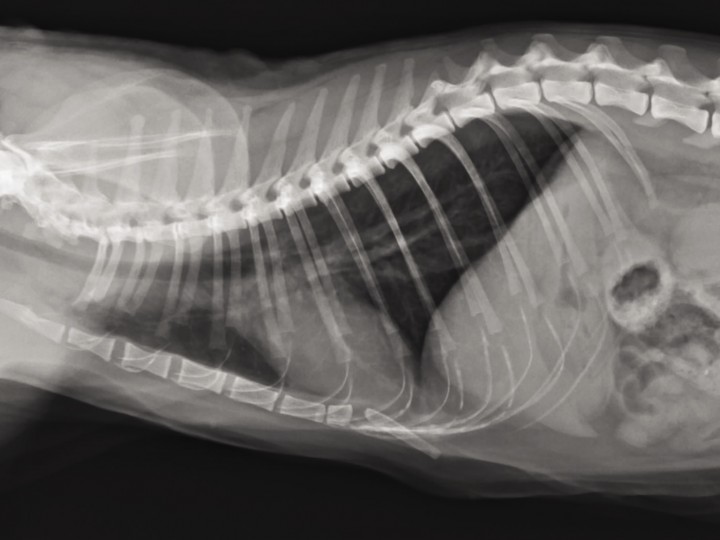

Las radiografías torácicas mostraron un patrón broncointersticial compatible con una bronquitis, evidenciando que, además de rinitis, el paciente presentaba una alteración de las vías respiratorias bajas (Fig. 8).

<p>Radiografía torácica lateral derecha con patrón broncointersticial.</p>

Figura 8

Radiografía torácica lateral derecha con patrón broncointersticial.